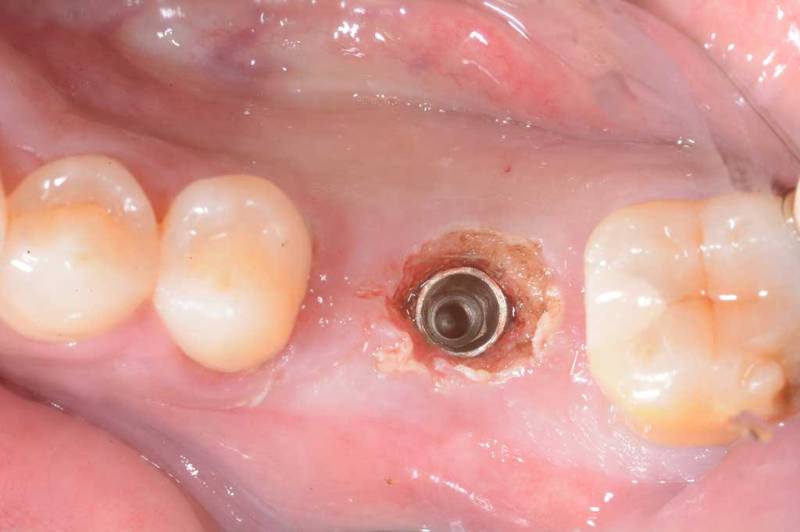

微創植牙術前

微創植牙術中

微創植牙術後